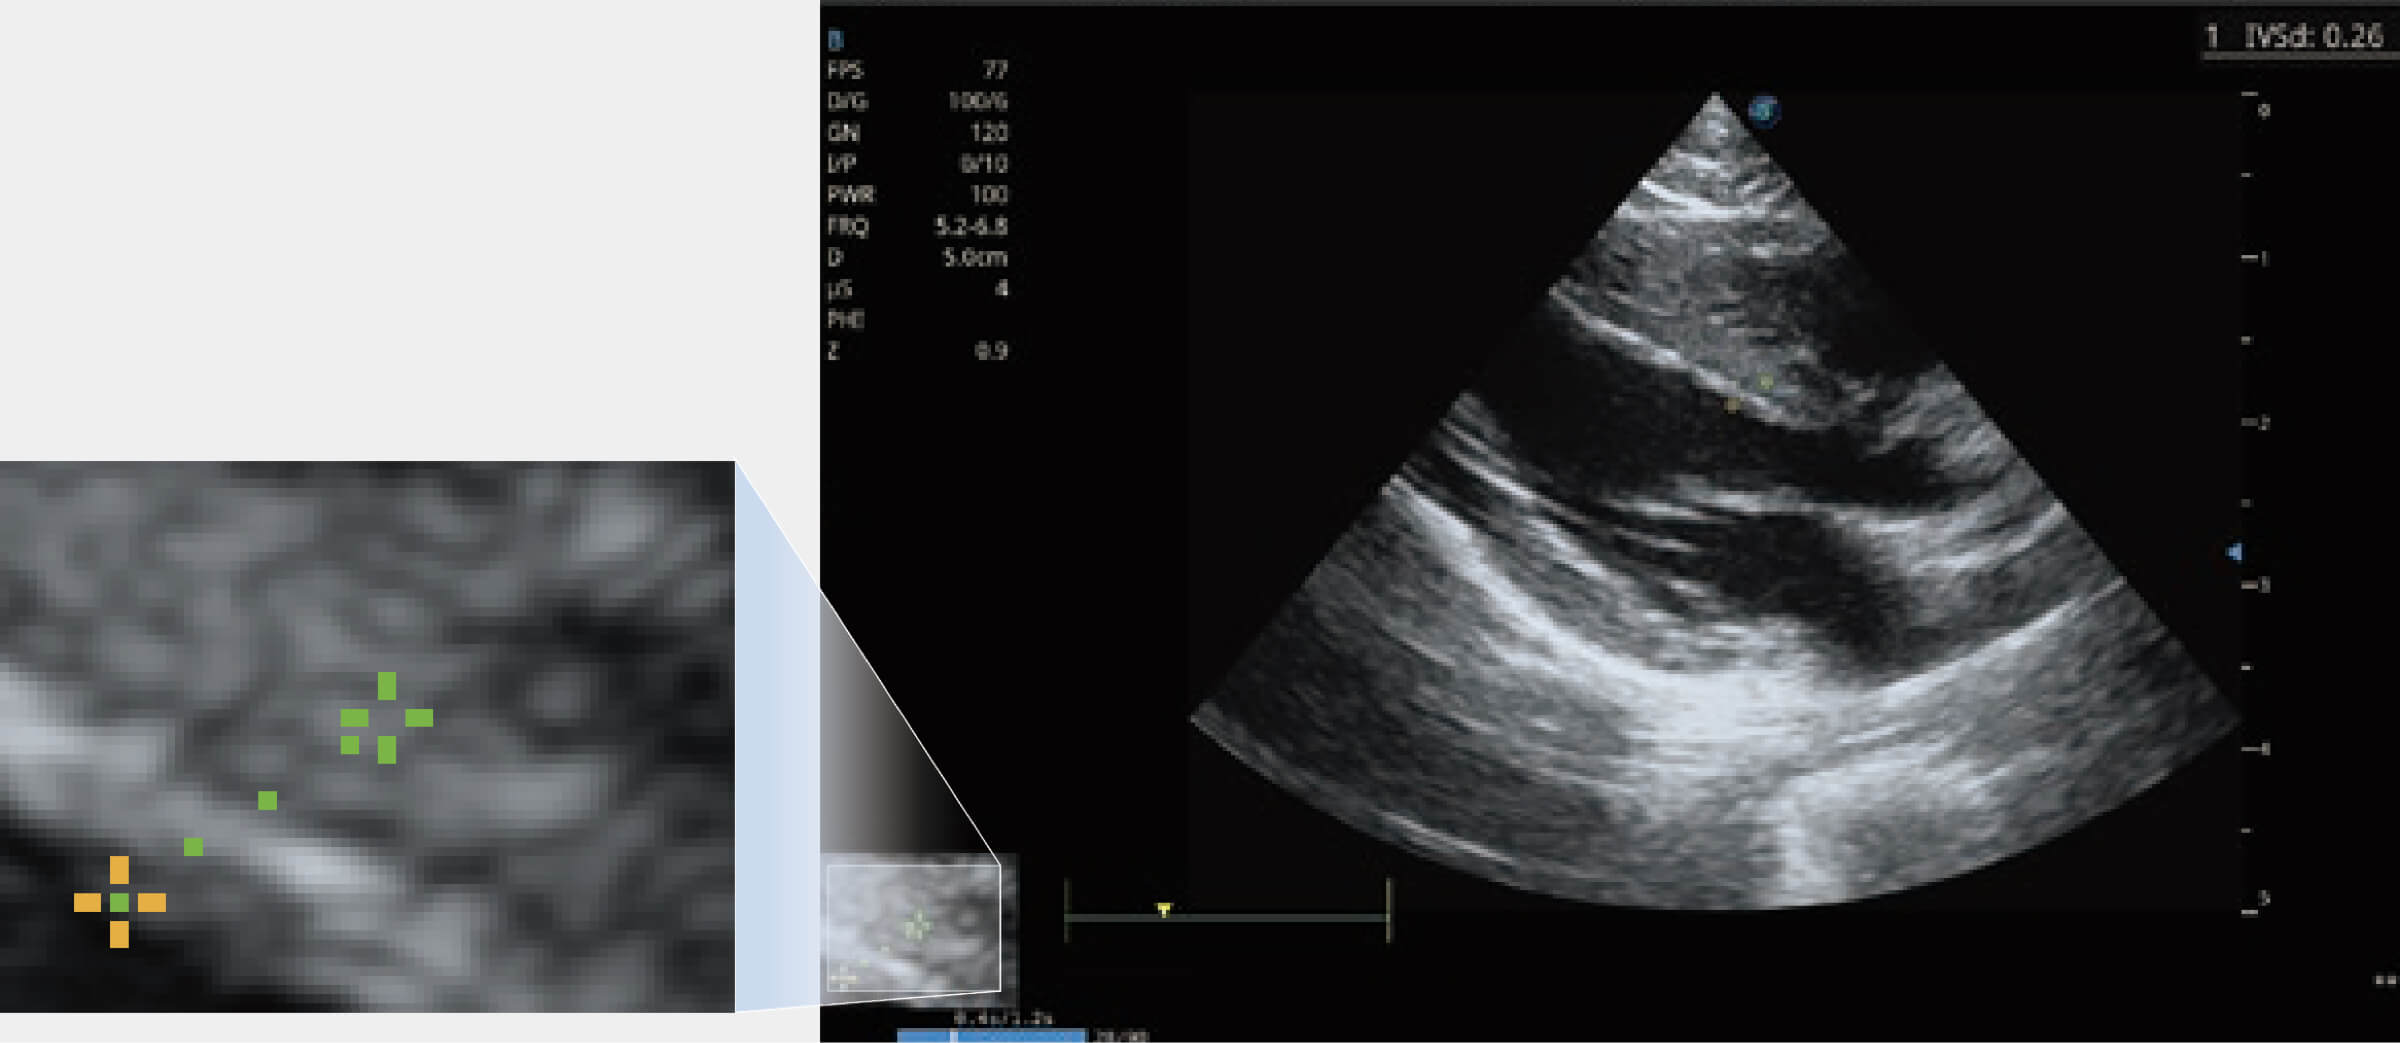

ProPet 70 進(jìn)一步提升了微米成像算法,更加注重對基礎(chǔ)原始圖像的還原和保留,在有效減少斑點(diǎn)噪聲、增強(qiáng)組織邊界顯示的同時(shí),避免過度優(yōu)化丟失真實(shí)的解剖信息。

能夠基于左心室壁追蹤和辛普森法,自動計(jì)算射血分?jǐn)?shù),支持多個可移動點(diǎn)描跡,與手動測量相比,極大節(jié)省了動物醫(yī)生的時(shí)間和精力。

通過360度任意調(diào)節(jié)3條M型取樣線,在同一心動周期上觀察心臟不同位置的運(yùn)動曲線,得到準(zhǔn)確的心功能測量數(shù)據(jù),有效評估心肌運(yùn)動及左心室功能。

當(dāng)心臟測量結(jié)果超出正常范圍時(shí),可實(shí)時(shí)預(yù)警提示動物醫(yī)生,減少疾病漏診概率。